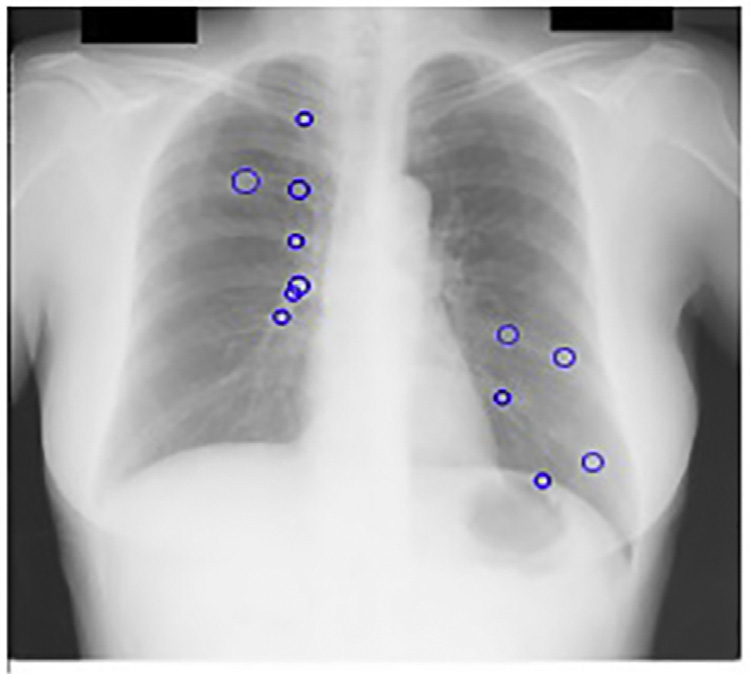

采用PCA滤波作为预处理步骤的CAD方案输出(图14.19)。PCA滤波抑制了肋骨,从而消除了发生在肋骨上的假阳性。PCA滤波还增强了被肋骨遮挡的结节。

kNN分类被添加为第三个后处理步骤,进一步将每幅图像检测到的结节数量减少至13个。图14.16展示了为JSRT数据库构建的特征空间,其中特征是之前定义的选定特征。图14.19展示了我们的计算机辅助诊断系统在kNN分类后的输出结果。

我们的最终第四种策略是将主成分分析滤波后的肋骨抑制图像作为计算机辅助诊断系统的输入。图14.20中可明显看到肋骨抑制的效果。采用主成分分析滤波后,每幅图像保留的候选结节平均数量降至三个。在肋骨边缘会检测到大量假阳性,而当输入为肋骨抑制图像时,这些假阳性被有效去除。此外,主成分分析滤波还提高了计算机辅助诊断系统的敏感性,因为被肋骨遮挡的癌结节变得更加显著。